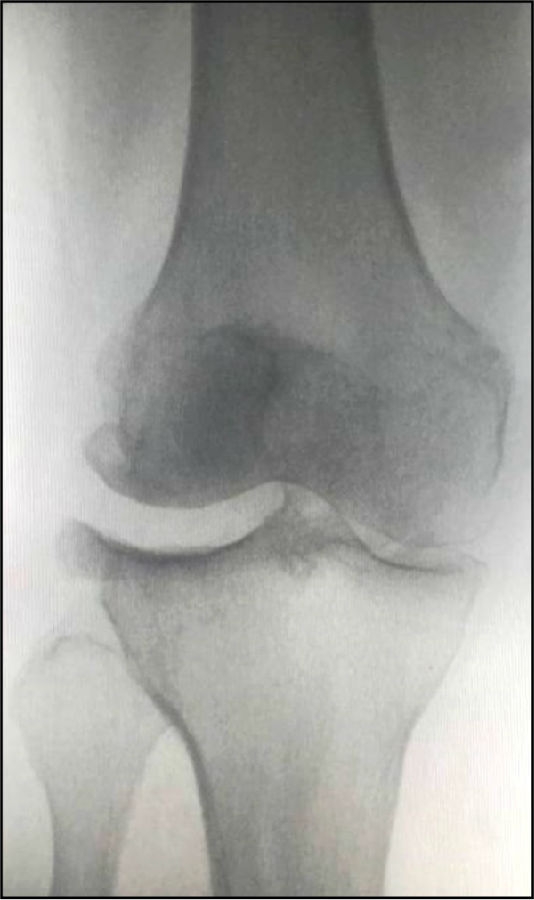

Case2:二期Bi-UKA治疗进展性OA

术前影像

术后5年,外侧进展性OA

LUKA治疗外侧进展性OA